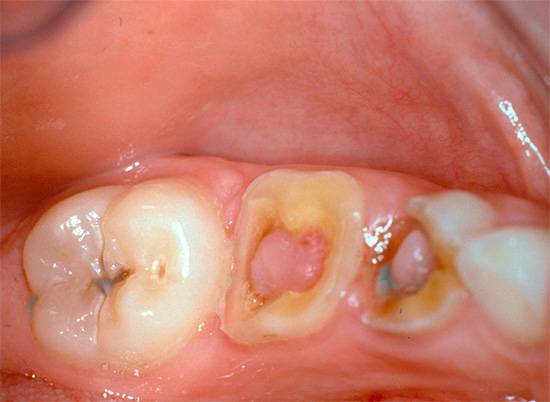

Più spesso trovato in odontoiatria pulite fibrosa cronica (in quasi il 70% dei casi), meno spesso - cancrenoso. Non si verifica quasi mai negli adulti, polmonite ipertrofica, diagnosticata solo occasionalmente all'appuntamento con un dentista pediatrico.

Nella pulpite ipertrofica cronica, il dente, di regola, è leggermente preoccupato. Il sintomo principale in questo caso è il dolore doloroso durante la masticazione di cibi solidi e raramente da irritanti della temperatura. A volte si osserva sanguinamento del dente durante il pasto, che è associato alla crescita nella carie cavità della polpa del tipo di "carne selvatica" e alla sua lesione meccanica. È questo sintomo di polmonite cronica che spesso spaventa una persona, costringendola a cercare aiuto alla fine.

Se c'è un messaggio con una cavità cariata e compaiono dolore e sanguinamento quando si sondano con una sonda acuta, allora con un alto grado di probabilità è cronico pulite fibrosa. Con un cambiamento nel colore dei denti, l'aspetto di un'ombra grigia, con una grande quantità di tessuto cariato ammorbidito nella cavità del dente, quando il "nervo" viene parzialmente distrutto e il dolore si verifica solo quando si sondano i canali, allora è molto probabilmente una polpite cranica cronica. La comparsa di tessuto troppo cresciuto all'interno della cavità in combinazione con l'indolenzimento quando lo sondano il più delle volte indica una polpite ipertrofica cronica.